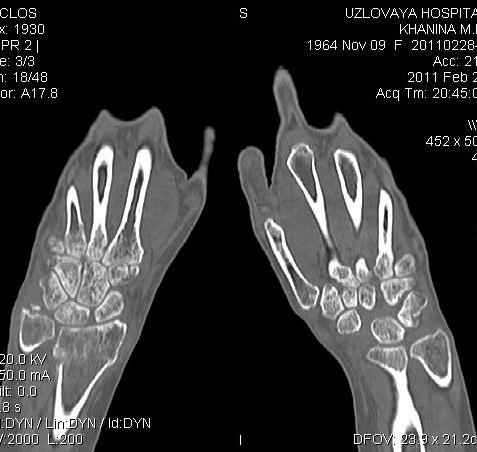

Уважаемые коллеги.Прошу обсудить случай лечения перелома дистального метаэпифиза лучевой кости. Ситуация скандальная и крайне неблагоприятная. Больная с патологической обстоятельностью мышления, склонностью к сутяжничеству, патологическими умозаключениями, не поддающимися коррекции (см. психиатрию, правда офиц. диагноза нет). В данном случае есть ряд ошибок с нашей стороны, прежде всего в отношении качества ведения документации (за что получил административное взыскание, по делом мне дураку). В остальном- придерживались в лечении подхода классический советской школы. Так как умную операцию…… сами знаете… 15.12- перелом луча в Москве. Там же репозиция, гипс. Дальнейшее лечение у нас в ЦРБ. 20.12.- вторичное смещение в гипсе21.12- под внутривенным наркозом- репозиция, гипсовая лонгета. Дальше начинается самое интересное. После репозиции больная заявила, что я (репозицию делал я) порвал ей все связки в суставе, посинел у нее 5 палец, якобы я за него тянул и т. д. На самом деле на 2 сутки после репозиции рука немного отекла и было незначительное сдавление гипсом, который был ослаблен. Дальнейшее лечение консервативное. Через 6 недель- гипс снят, назначено ЛФК. Пациентка крайне недовольна. Говорит, что на снимке у нее выступает кость, я ей сломал руку и.т.д. В общем началось. Пациентка прочитала в интернете наверное все, что есть по данной травме.По заключениями рентгенологов и консультанта из КДЦ областной больницы - стояние отломков допустимое. Объективно говоря- снижена высота лучевой кости, диастаз лучелоктевого сочленения, и не сросся шиловидный отросток. однако на РКТ при сравнении с другой стороной- разница незначительная. Дальше в одной из больниц нашей области и одной из больниц Москвы (вроде бы КГБ 53) врачи сказали, что репозиция сделана плохо. Нужна операция (восстановить длину лучевой кости), даже один из них предложил РЕДРЕССАЦИЮ (хи-хи) с наложением аппарата Илизарова. Что это для данной больной- радость неописанная. (см. описание психического статуса). Ничем другим, кроме зарабатывания дешевого авторитета объяснить данный факт не могу.Кстати, у больной еще нейропатия локтевого нерва.Для разрешения конфликта больная направлена на консультацию в ЦИТО на 03.03.11.

2. По сравнению и без ! втор смещение незначительное.НЕТ НИКАКОЙ ,,локтевой косорукости,,маделунгов . но имеется смещение совести у врачей КГБ 35--НЕТ ЗДОРОВЫХ, есть только недообследованные ! Этому смещению аппарат внешней фиксации не поможет .Психопаткам в менопаузе да весной только этого и надо чуть толкнули и поехало .

Заключение: Консолидированный в неправильном положении перелом дистального метафиза левой лучевой кости. Ротационная контрактура левого предплечья. Рекомендовано- разработка, консультация через 2 месяца.